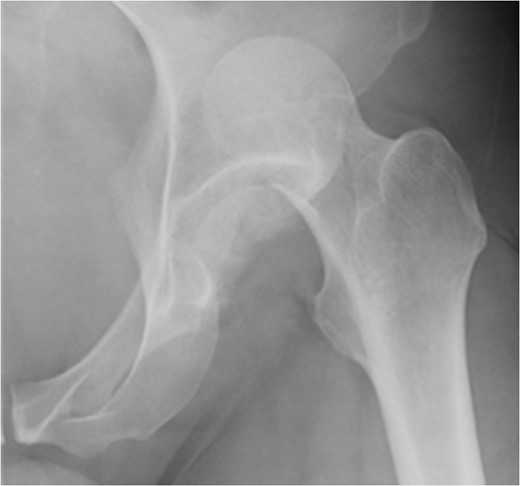

A fit and well man in his 40s had fallen while hiking up a steep hill. He complained of immediate onset, severe left hip pain and inability to move. He was airlifted to our hospital and was found to have shortened externally rotated left leg. Plain X-rays were performed in the emergency department (Fig. 1) identifying isolated fracture–dislocation of the left hip. Computed tomography (CT) was performed while en route to theatre (Figs 2 and 3).

AP radiograph of left hip showing fracture–dislocation of femoral head.